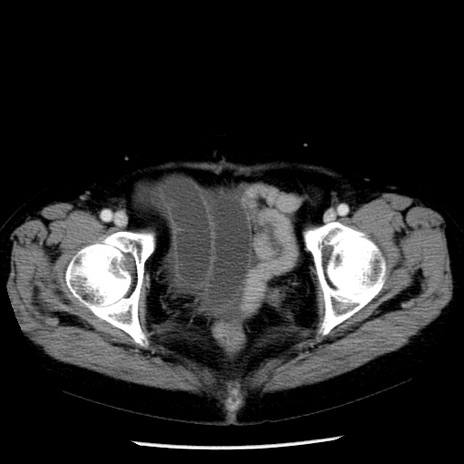

症例13(横断像)

【症例】70歳代女性

【主訴】腹痛、嘔吐

【現病歴】15時間程前(昨晩)より腹痛あり。今朝になっても症状の改善なく、嘔吐あり。腹痛も増悪あり、救急外来受診。

【既往歴】子宮癌全摘術後

【身体所見】意識清明、BP 121/72mmHg、P 74bpm、SpO2 100%(RA)、腹部:平坦・軟、腸雑音ほぼ聴取せず。下腹部・心窩部・臍左上に圧痛あり。反跳痛なし。

【データ】WBC 10600、CRP 0.15